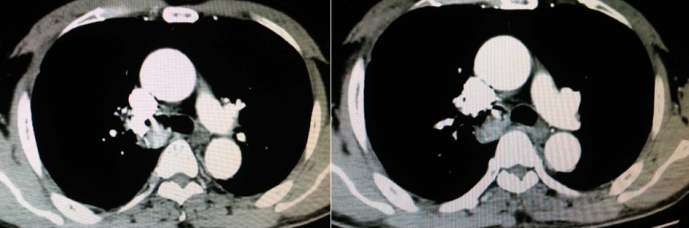

病例3(上海长海医院病例),中年男性,慢性起病。反复咳嗽、咳痰3年余,加重1个月。胸部CT提示右主支气管新生物。

图片

支气管镜检查发现右主支气管有菜花样宽基底赘生物。

胸部CT增强扫描右主支气管分布强化的血管影。